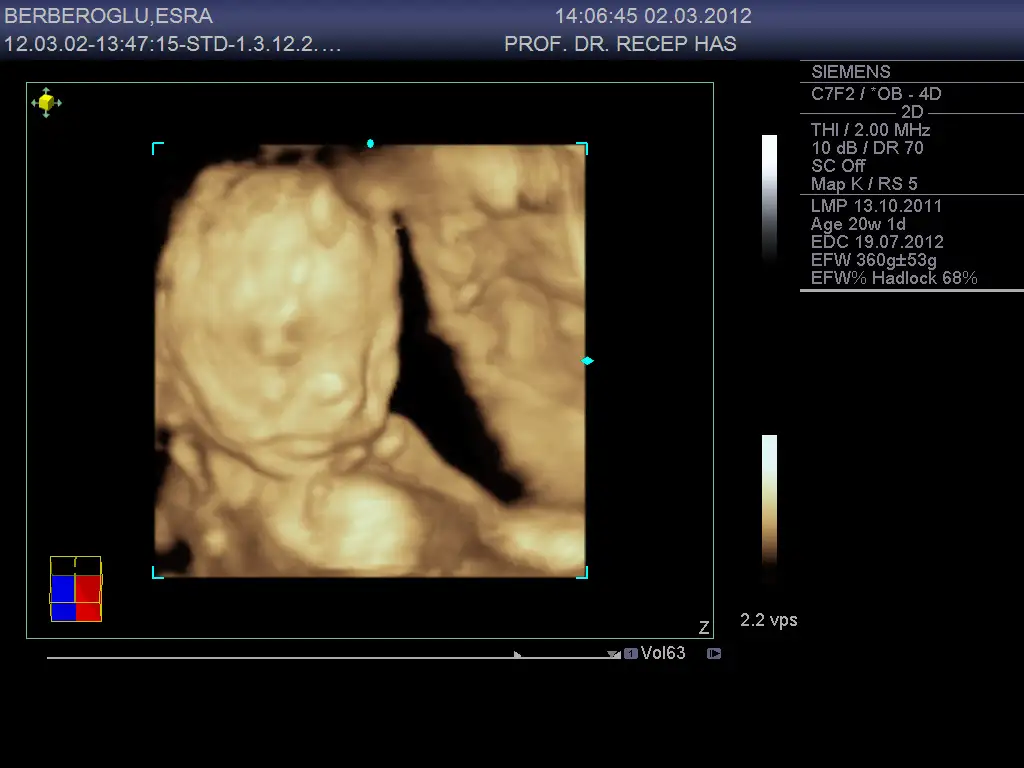

canım nasılsın, bizim ayrıntılı sonuçlarımız çok iyi çıktı, normal yani herhangi bir sorun yok, bebişim 24 cm/360 gr. olmuş teyzesi, fotosunu ve videosunu aldık izleyip duruyorum.